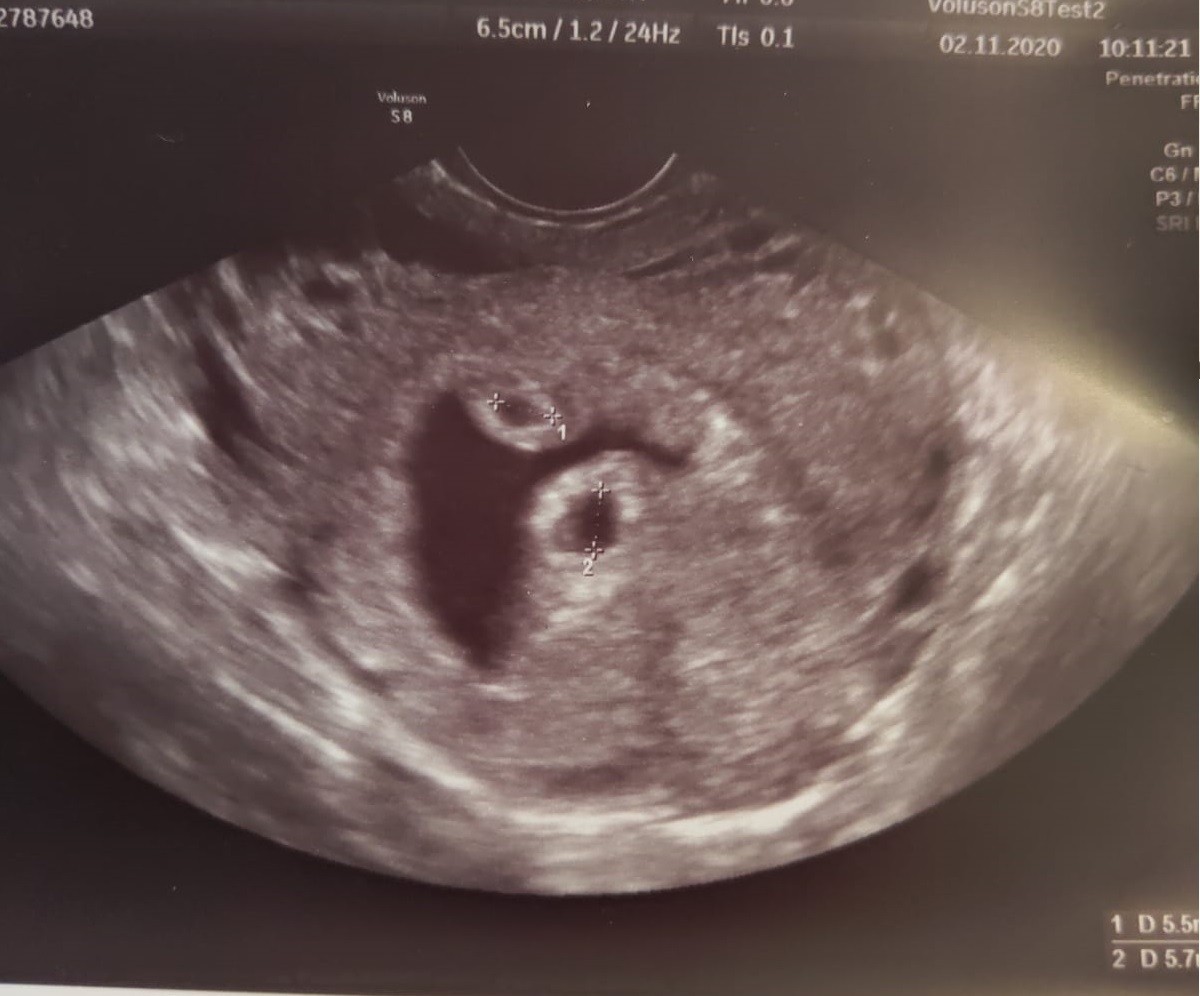

tak to wygląda, jest go niestety sporo.

Zarodeczki mają tu po 6 mm, wiec łatwo policzyć ile mniej wiecej jest płynu.